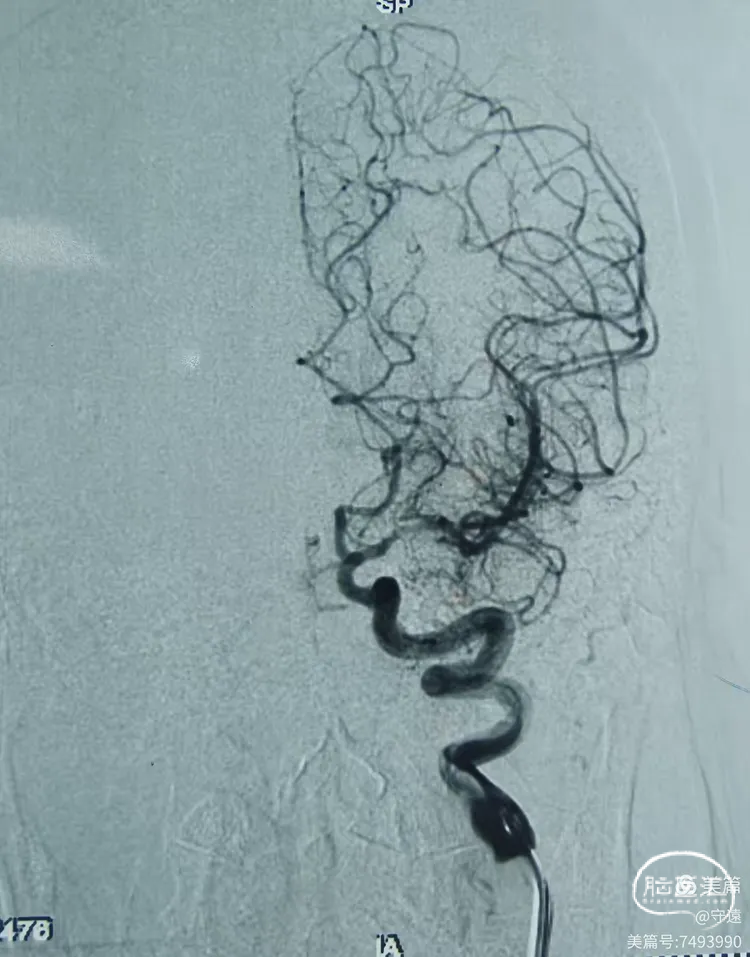

造影显示:左侧大脑中动脉M1以远末显影。

动脉晚期皮层支代偿供血良好,返流至M1段分叉部。

影像评估:M1段闭塞,分叉以远血管床显影良好。

2.造影显示M1闭塞,动脉晚期皮层支返流至M1分叉部。说明闭塞段在M1中段至分叉部。